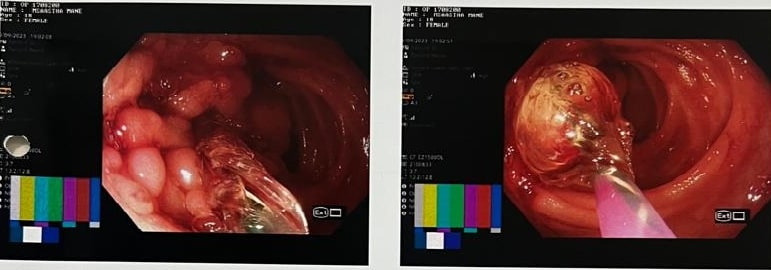

3. Difficulty in swallowing : This is considered as a serious symptom at any age group.

Difficulty in Swallowing

This can be due to severe acidic ulcerations, narrowing of the food passage due to non cancer or

cancerous lesion or pressure on the food pipe from outside.

Cancerous Lesion - Balloon Dilatation as a Palliative Treatment